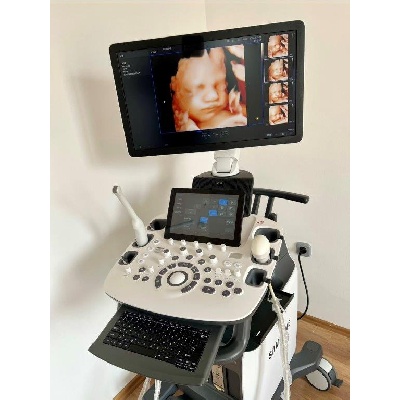

Használt Samsung HERA I10 szülészeti-nőgyógyászati ultrahang készülék

| Gyártó: | SAMSUNG MEDISON |

|---|---|

| Pontos típus: | USS-HRI1F40/WR |

| Gyártás éve: | 2019 |

| Irányár (bruttó): | 18.000.000,- Ft |

| Műszaki állapot: | Kifogástalan |